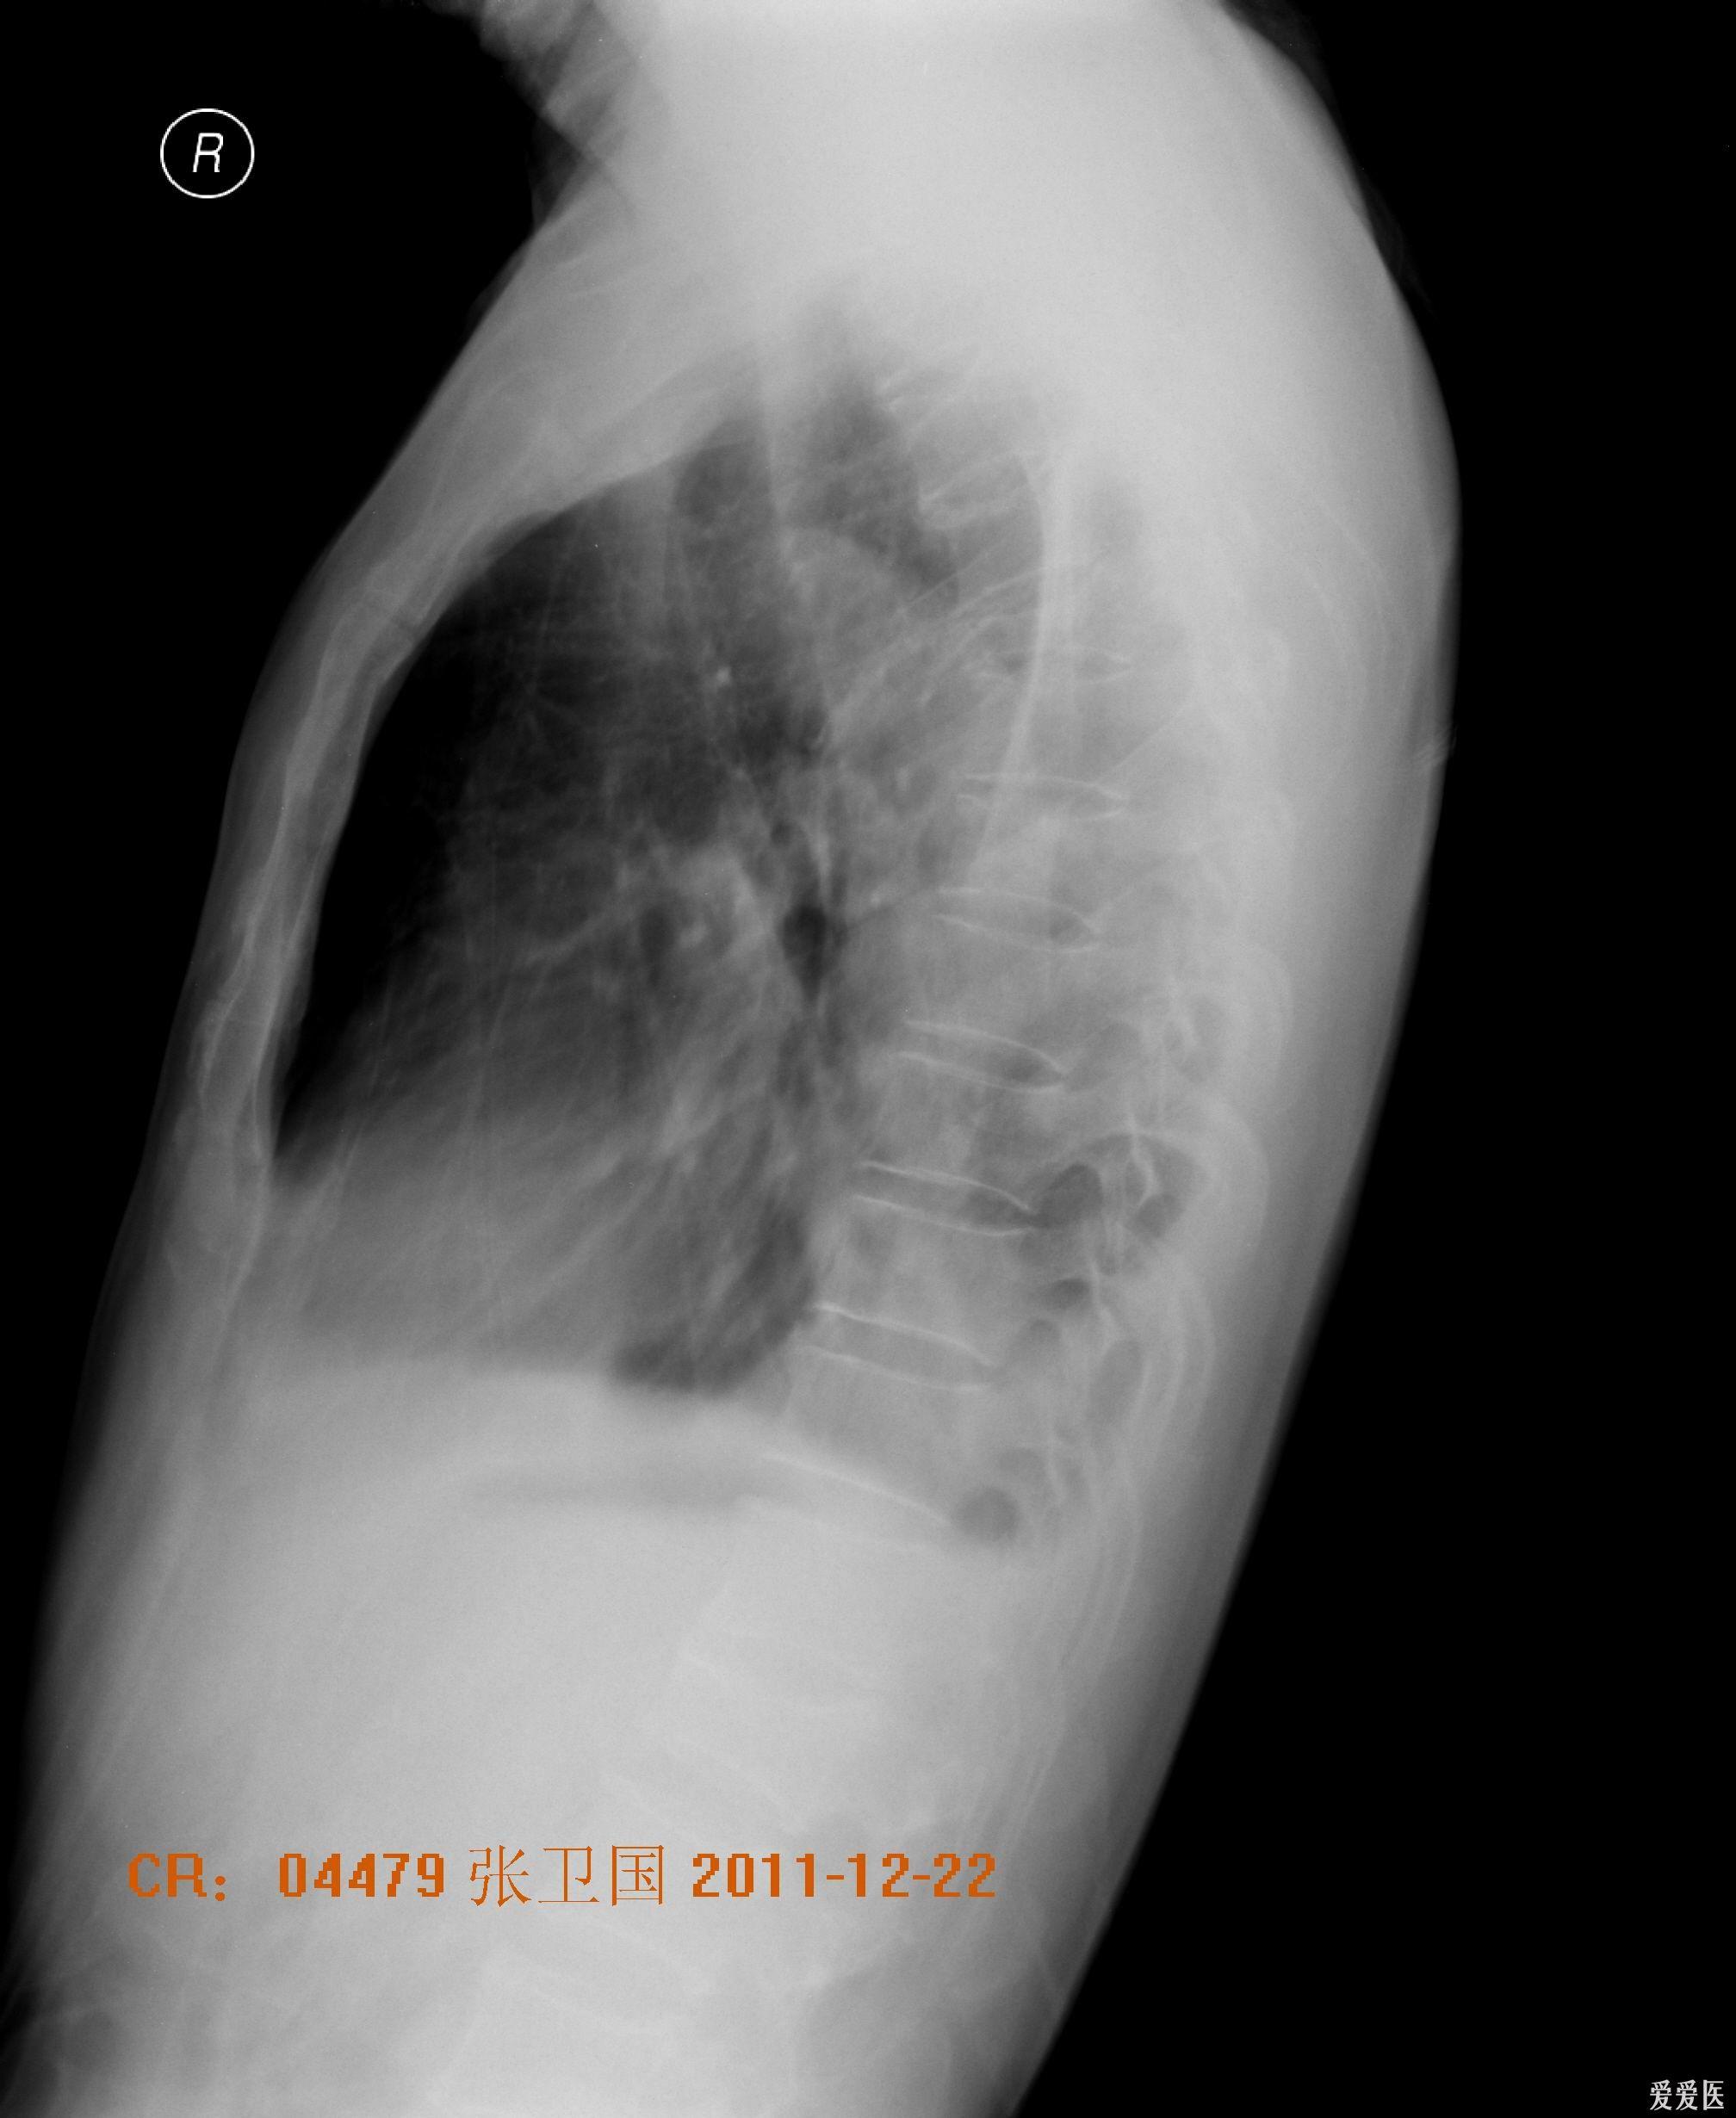

外伤后肺不张 医学影像学讨论版 爱爱医医学论坛

肺不张胸片

肺不张ct

肺不张胸片表现